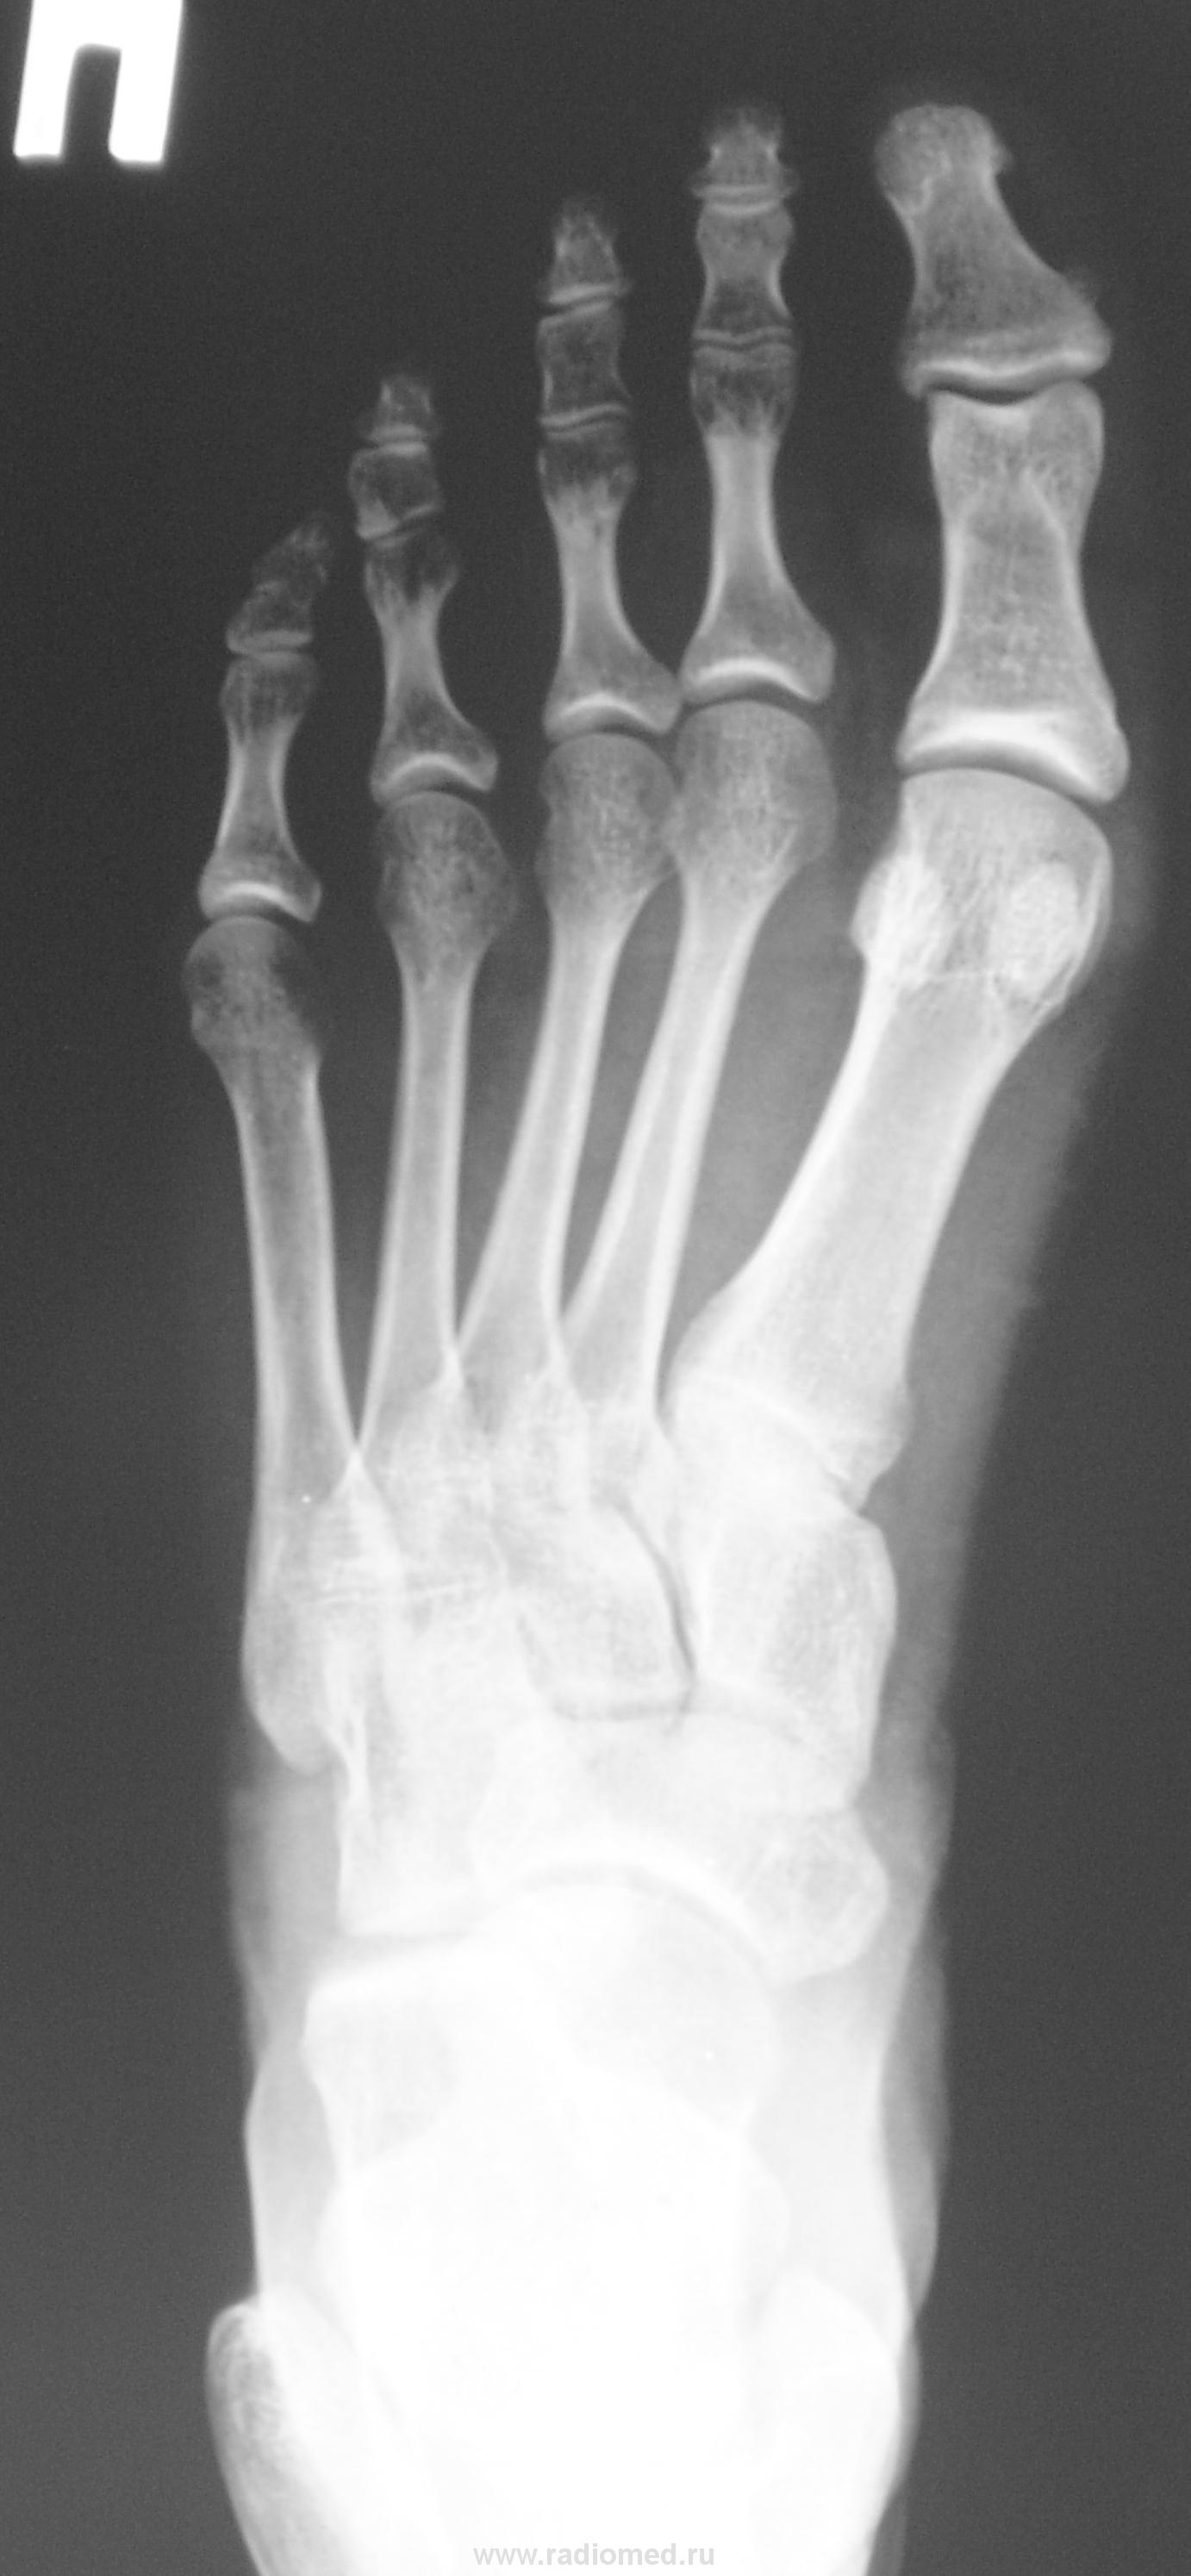

Молодая женщина. Беспокоят боли в ступнях по подошвенной поверхности, больше слева.

Правая стопа сделана больше для сравнения.

Остеохондропатия сесамовидной кости 1 пл/фал.сустава левой стопы.

Спасибо. Но, вот почему она увеличена?

Весьма патогномоничной является рентгенологическая картина третьей стадии заболевания - стадии фрагментации. Пораженный отдел кости уже не дает гомогенной тени, а состоит из нескольких темных бесструктурных изолированных фрагментов неправильной формы. Светлые участки, на фоне которых видны эти фрагменты, соответствуют разрастаниям соединительной ткани и хряща между некротическими массами. Высота пораженного отдела кости уменьшается. Длительность третьей стадии составляет от полугода до двух с половиной лет, а иногда и более. Вероятно Валентин Львович, дама не сидит, а ходит, постоянная нагрузка веса тела делает свое дело.

И почему кость (сесамовидная) так увеличилась в размерах?

"На рентгенограмме-типичная дезорганизация структурного рисунка несколько иногда увеличенной косточки с фрагментацией её тени.Регенеративные явления выражены незначительно,полного восстановления стуктуры не бывает"-С.А.Рейнберг т2 стр286.      (несколько иногда( в тексте))-это вероятно в данном случае.

несросшийся перелом сесамовидной слева